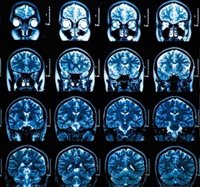

También, prosigue, es necesario potenciar las unidades clínicas de demencias, los bancos de cerebros, los estudios clínico-patológicos, los proyectos de neuroimagen anatómica y funcional y los centros clínicos que sustenten la investigación.